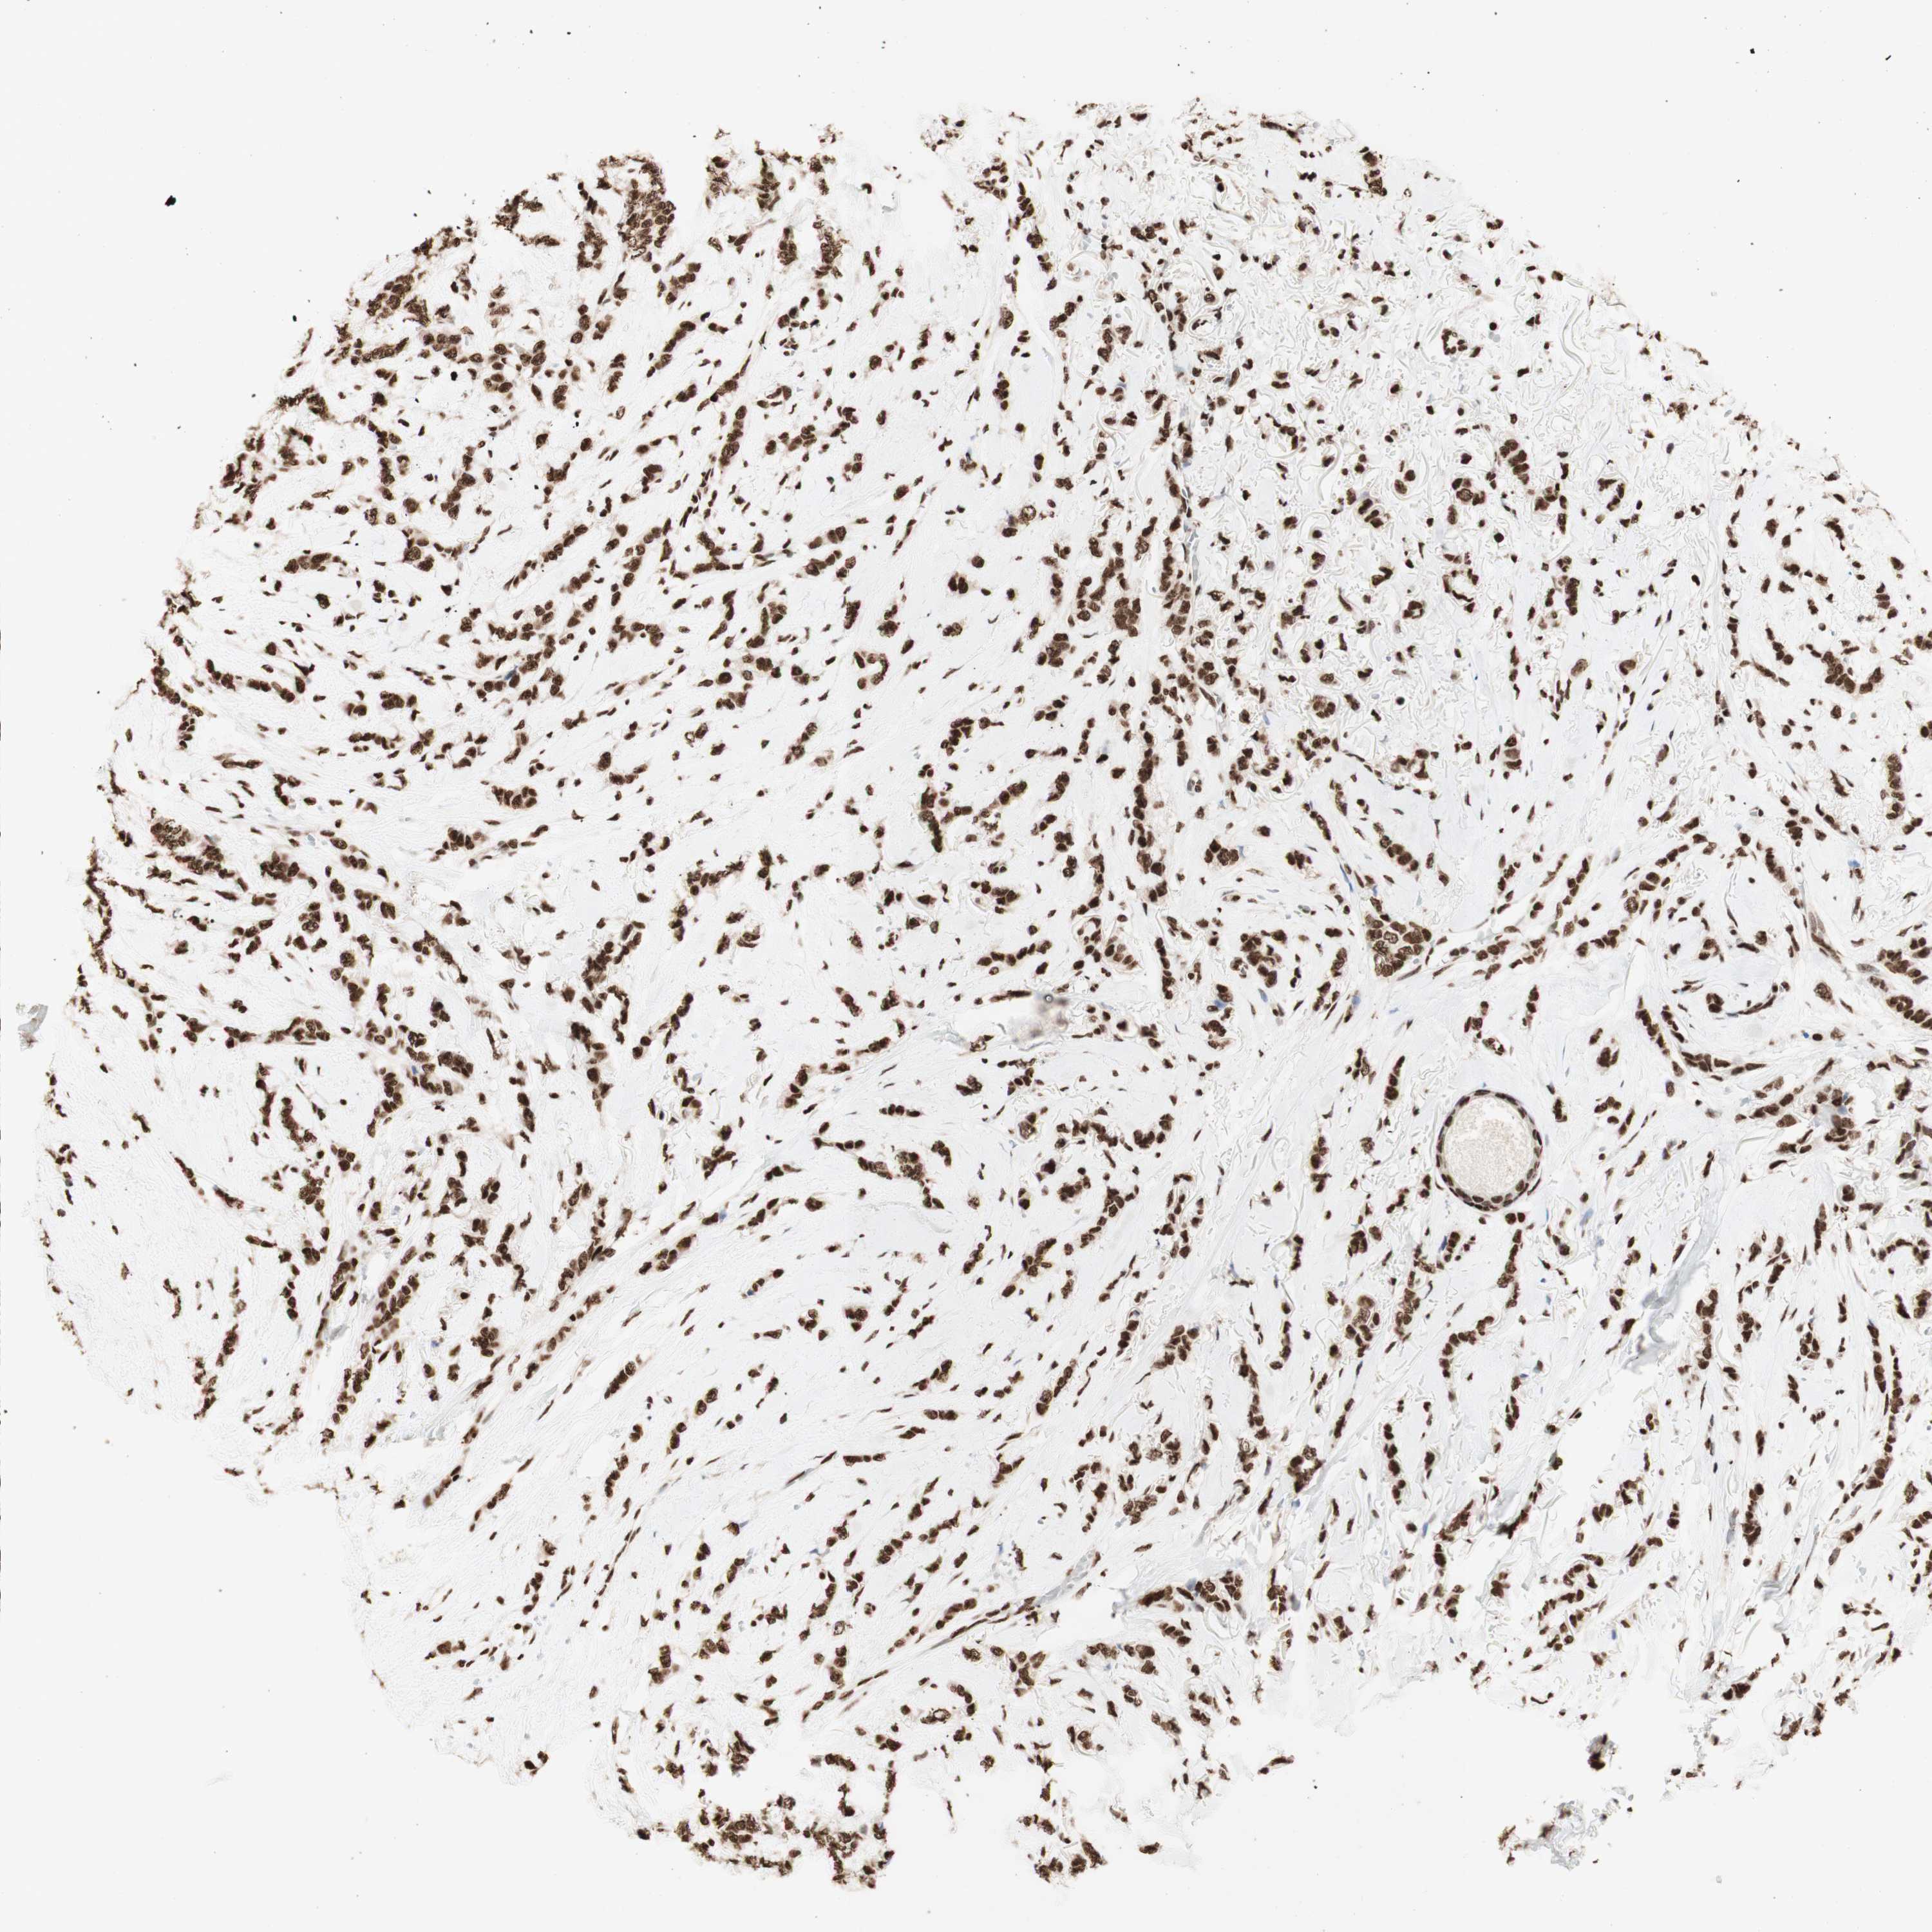

CANCER BREAST CANCER Show tissue menu

BRCA TCGA BRCA VALIDATION PROTEIN EXPRESSION